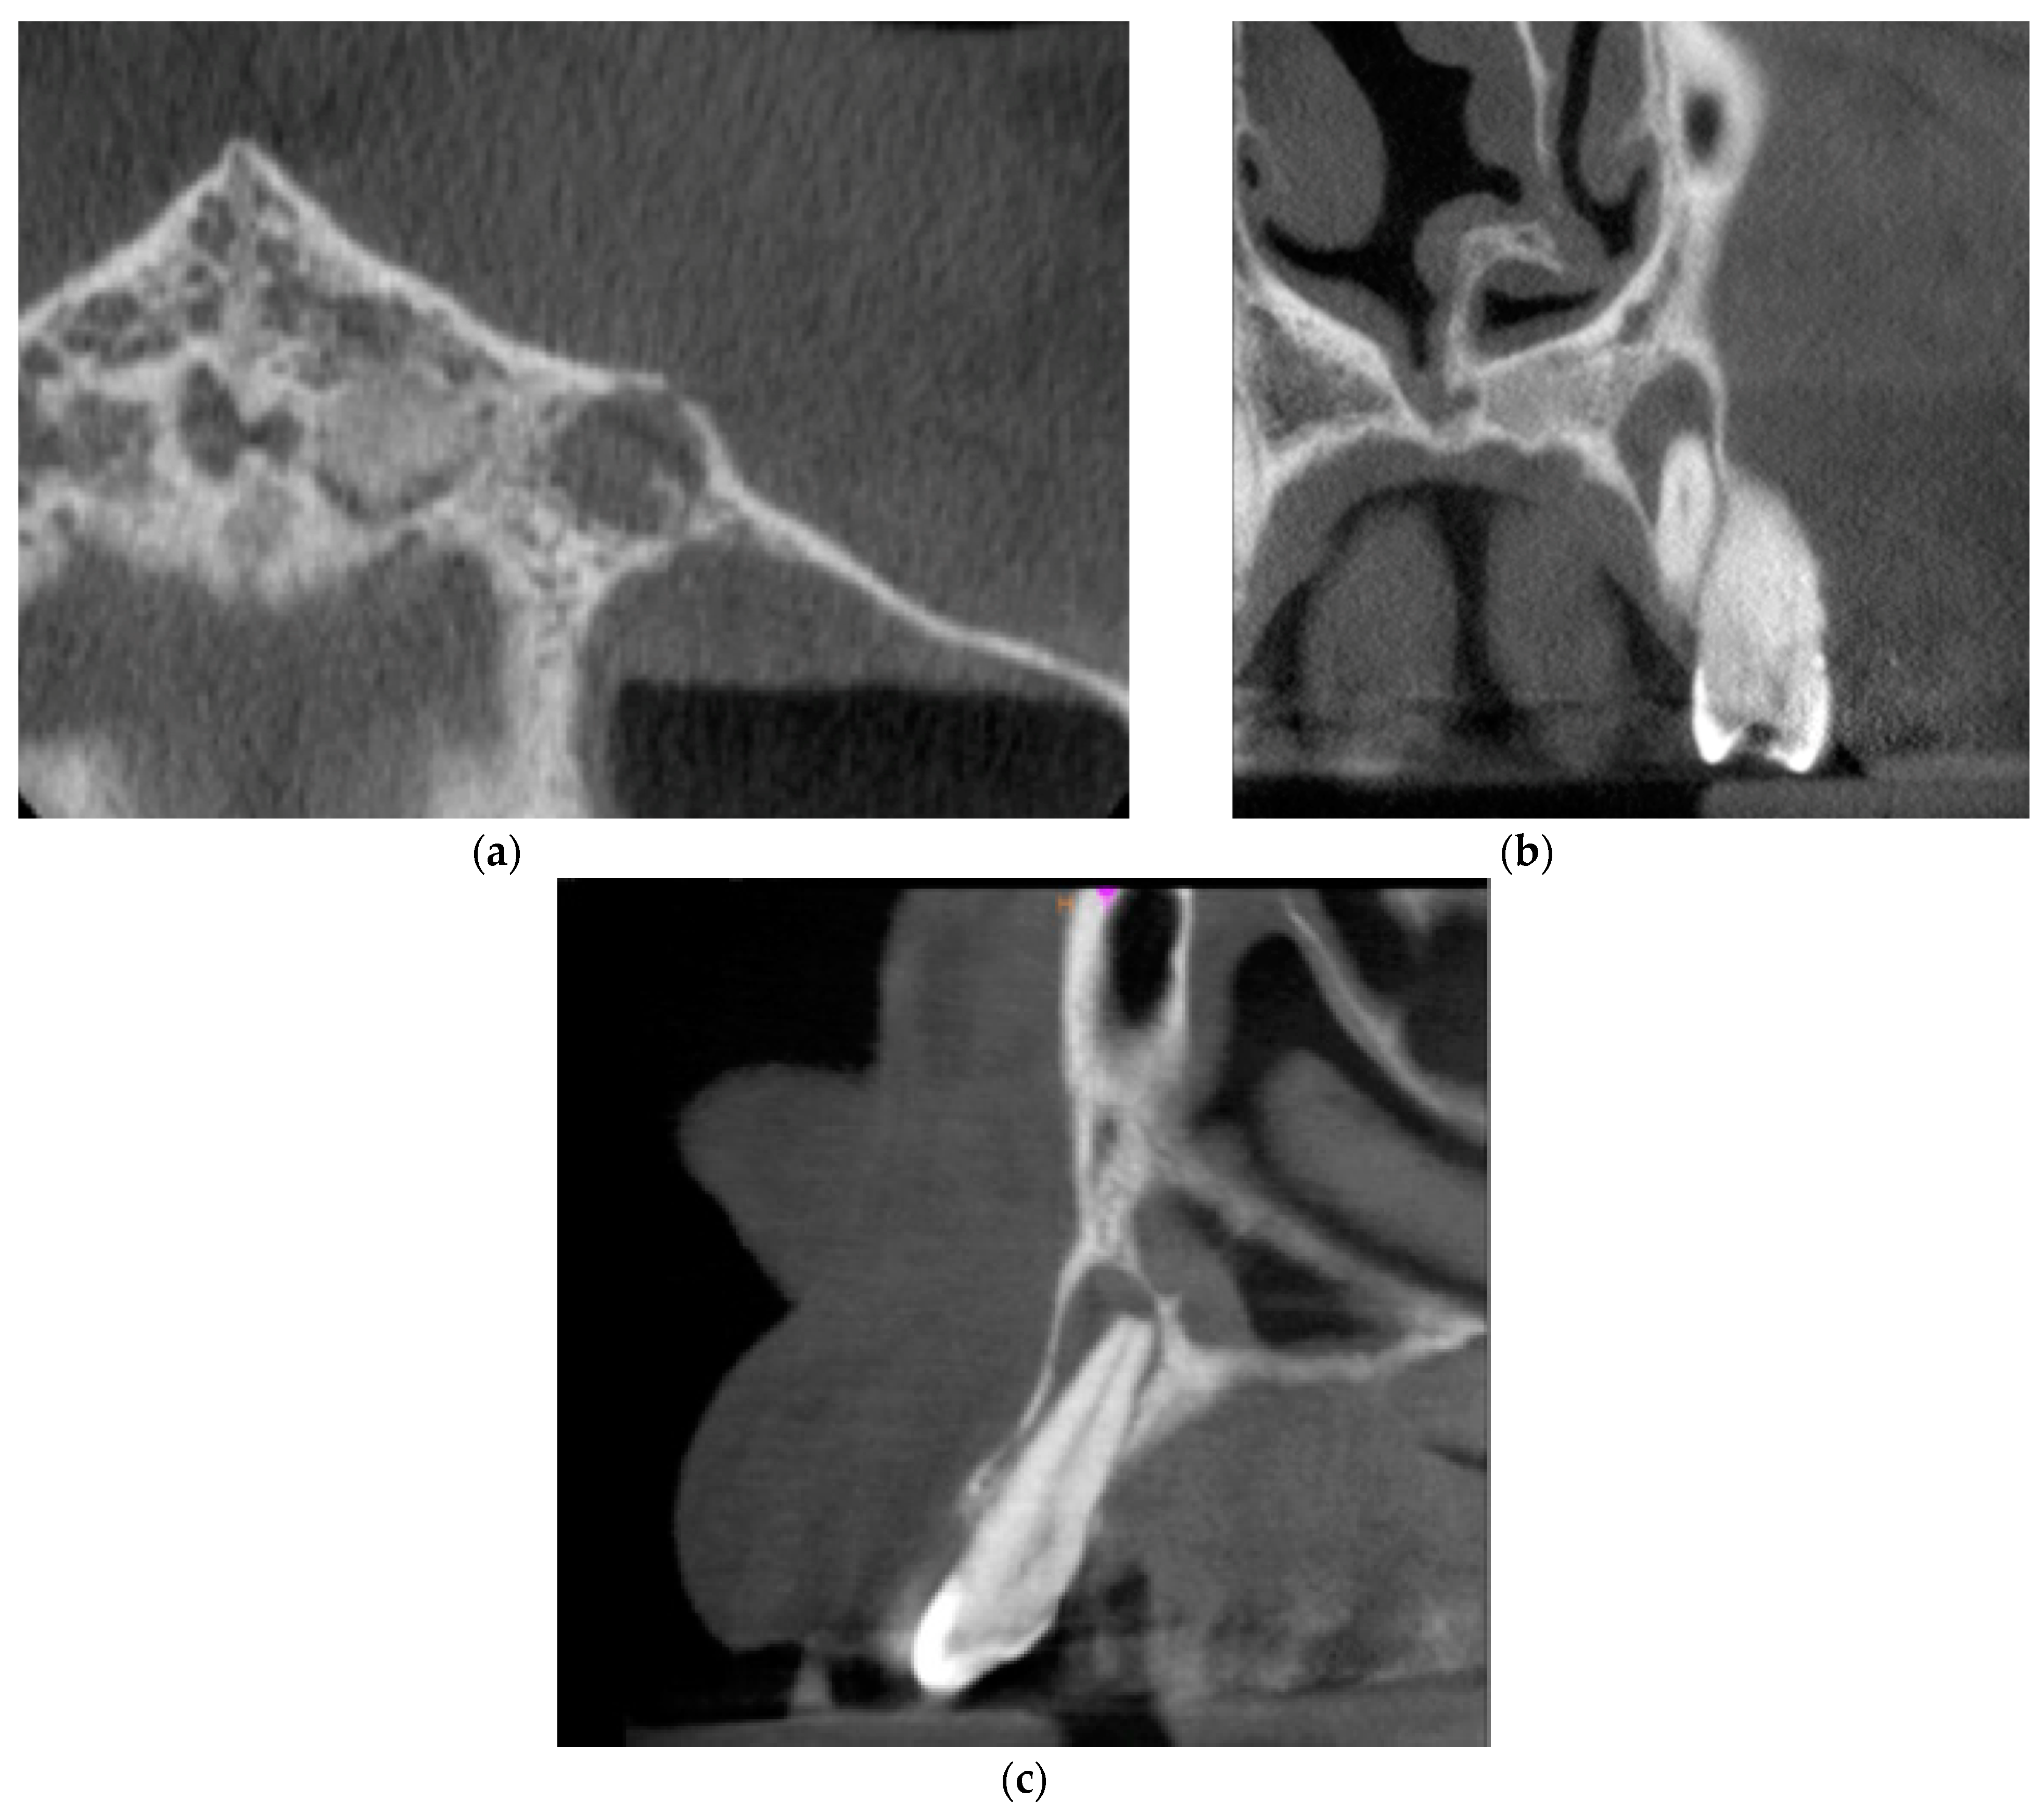

The CBCT of tooth 23 was taken. The periapical lesion was also measured with the use of CS 3D Imaging v3.5.18 Software (Carestream Health Inc., Trophy, Croissy-Beaubourg, France). The measured dimensions of the lesion were 12.7 × 8.7 × 6.4 mm. The CBCT images of the periapical lesion are presented in Figure 5.

Figure 5. Preoperative CBCT images presenting the periapical lesion around the root of tooth no. 23 (date of CBCT examination: 19 January 2021): (a) axial view; (b) coronal view; and (c) sagittal view.